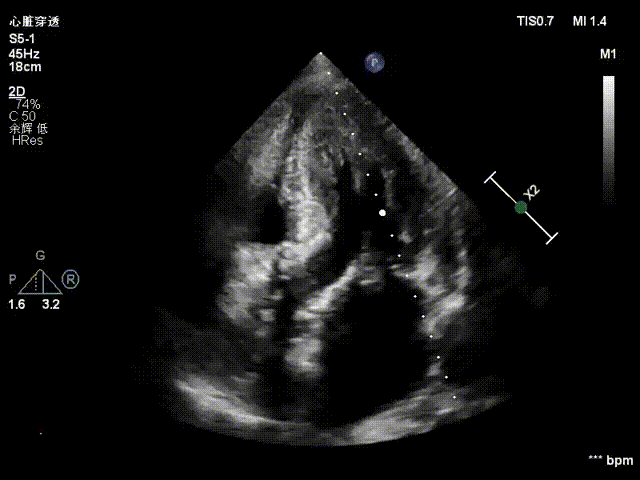

TTE入院

TTE